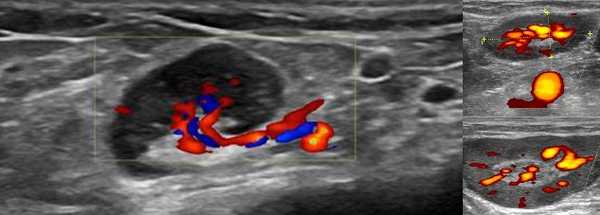

- Цветовой допплер: хиларная сосудистая система. Часто может нечетко отображать эхогенный хилум на градациях серого на УЗИ, но на допплеровских изображениях могут быть видны заметные хиларные сосуды. Хиларная васкуляризация может быть заметной, когда сосуды достигают периферии узла (т. е. начинаются в воротах и достигают периферии). Следует отличать периферическую сосудистую сеть в злокачественных и лимфоматозных узлах; новообразование, в которой возникает периферический кровоток

- Спектральный допплер: низкое сосудистое сопротивление [резистивный индекс (RI)